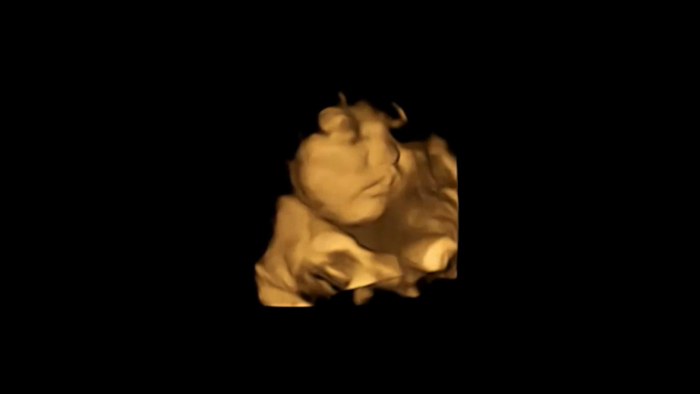

A study led by Durham University’s Fetal and Neonatal Research Lab , UK, took 4D ultrasound scans of 100 pregnant women to see how their unborn babies responded after being exposed to flavours from foods eaten by their mothers.

Researchers looked at how the fetuses reacted to either carrot or kale flavours just a short time after the flavours had been ingested by the mothers.

Fetuses exposed to carrot showed more “laughter-face” responses while those exposed to kale showed more “cry-face” responses.

The research team, which also included scientists from Aston University, Birmingham, UK, and the National Centre for Scientific Research-University of Burgundy , France, scanned the mothers, aged 18 to 40, at both 32 weeks and 36 weeks of pregnancy to see fetal facial reactions to the kale and carrot flavours.

Facial reactions seen in both flavour groups, compared with fetuses in a control group who were not exposed to either flavour, showed that exposure to just a small amount of carrot or kale flavour was enough to stimulate a reaction.